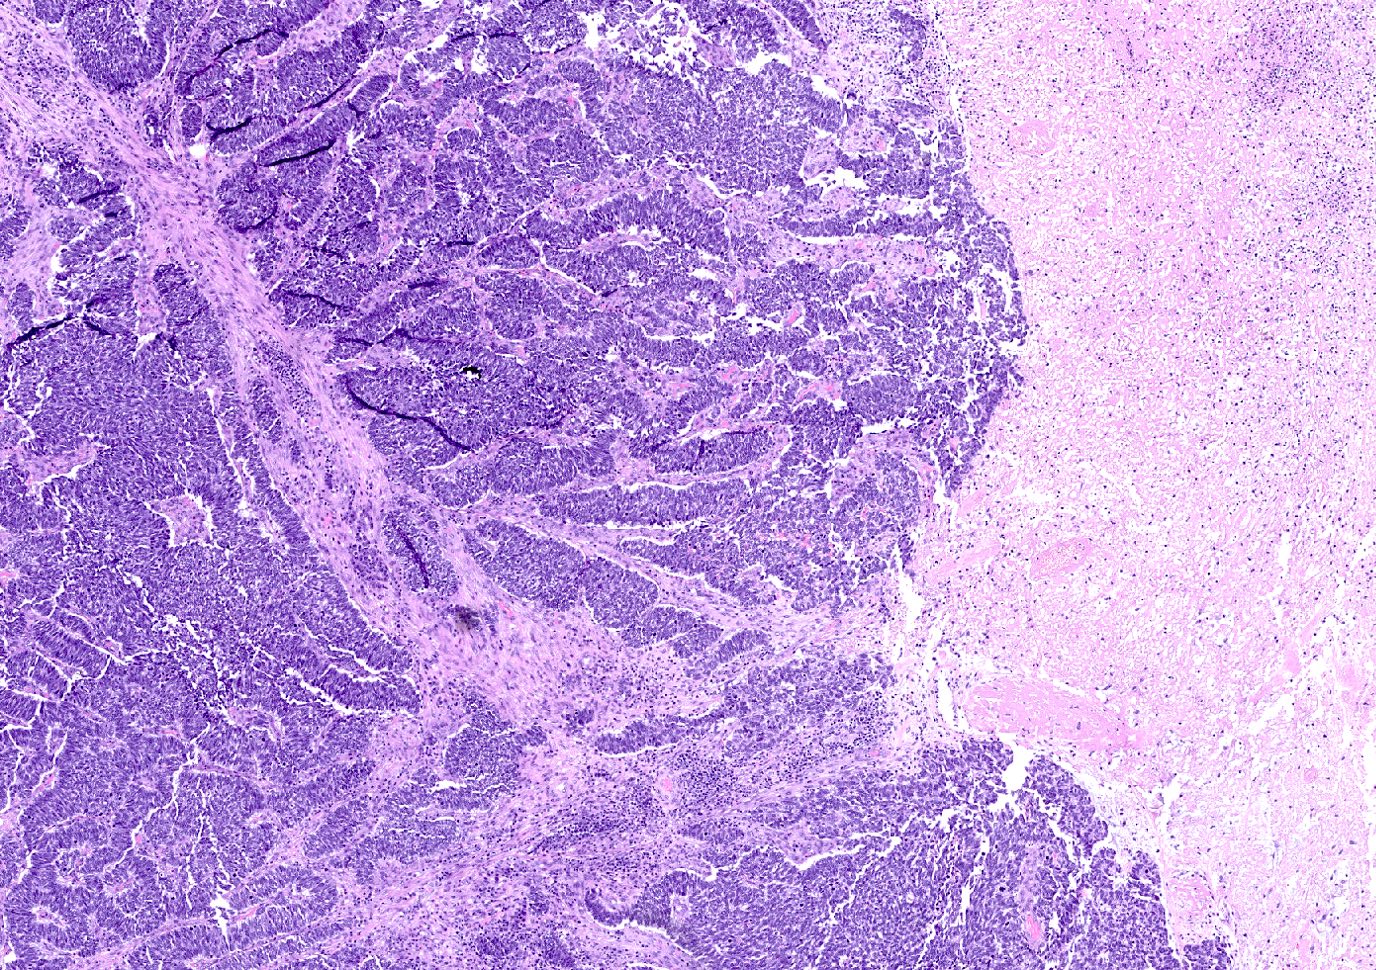

Contributed by Joshua J.X. Li, M.B.Ch.B., Gary M. Tse, M.B.B.S. and Kristen E. Muller D.O.

Small cell carcinoma

- Small cell carcinoma:

- Infiltrative growth pattern

- Crush artifact frequent

- Necrosis and lymphovascular invasion common

- Tumor cells densely packed with ill defined cell borders

- High N/C ratio with scanty cytoplasm

- Small dark hyperchromatic nuclei and inconspicuous nucleoli

- Mitotic count high

- Associated with proliferative changes, in situ carcinomas and invasive carcinomas (Am J Surg Pathol 2000;24:1231)

- In situ small cell carcinoma present in 5 out of 9 cases in a case series

- In situ / invasive ductal, lobular and squamous neoplastic components occasionally identified

- Infiltrative growth pattern